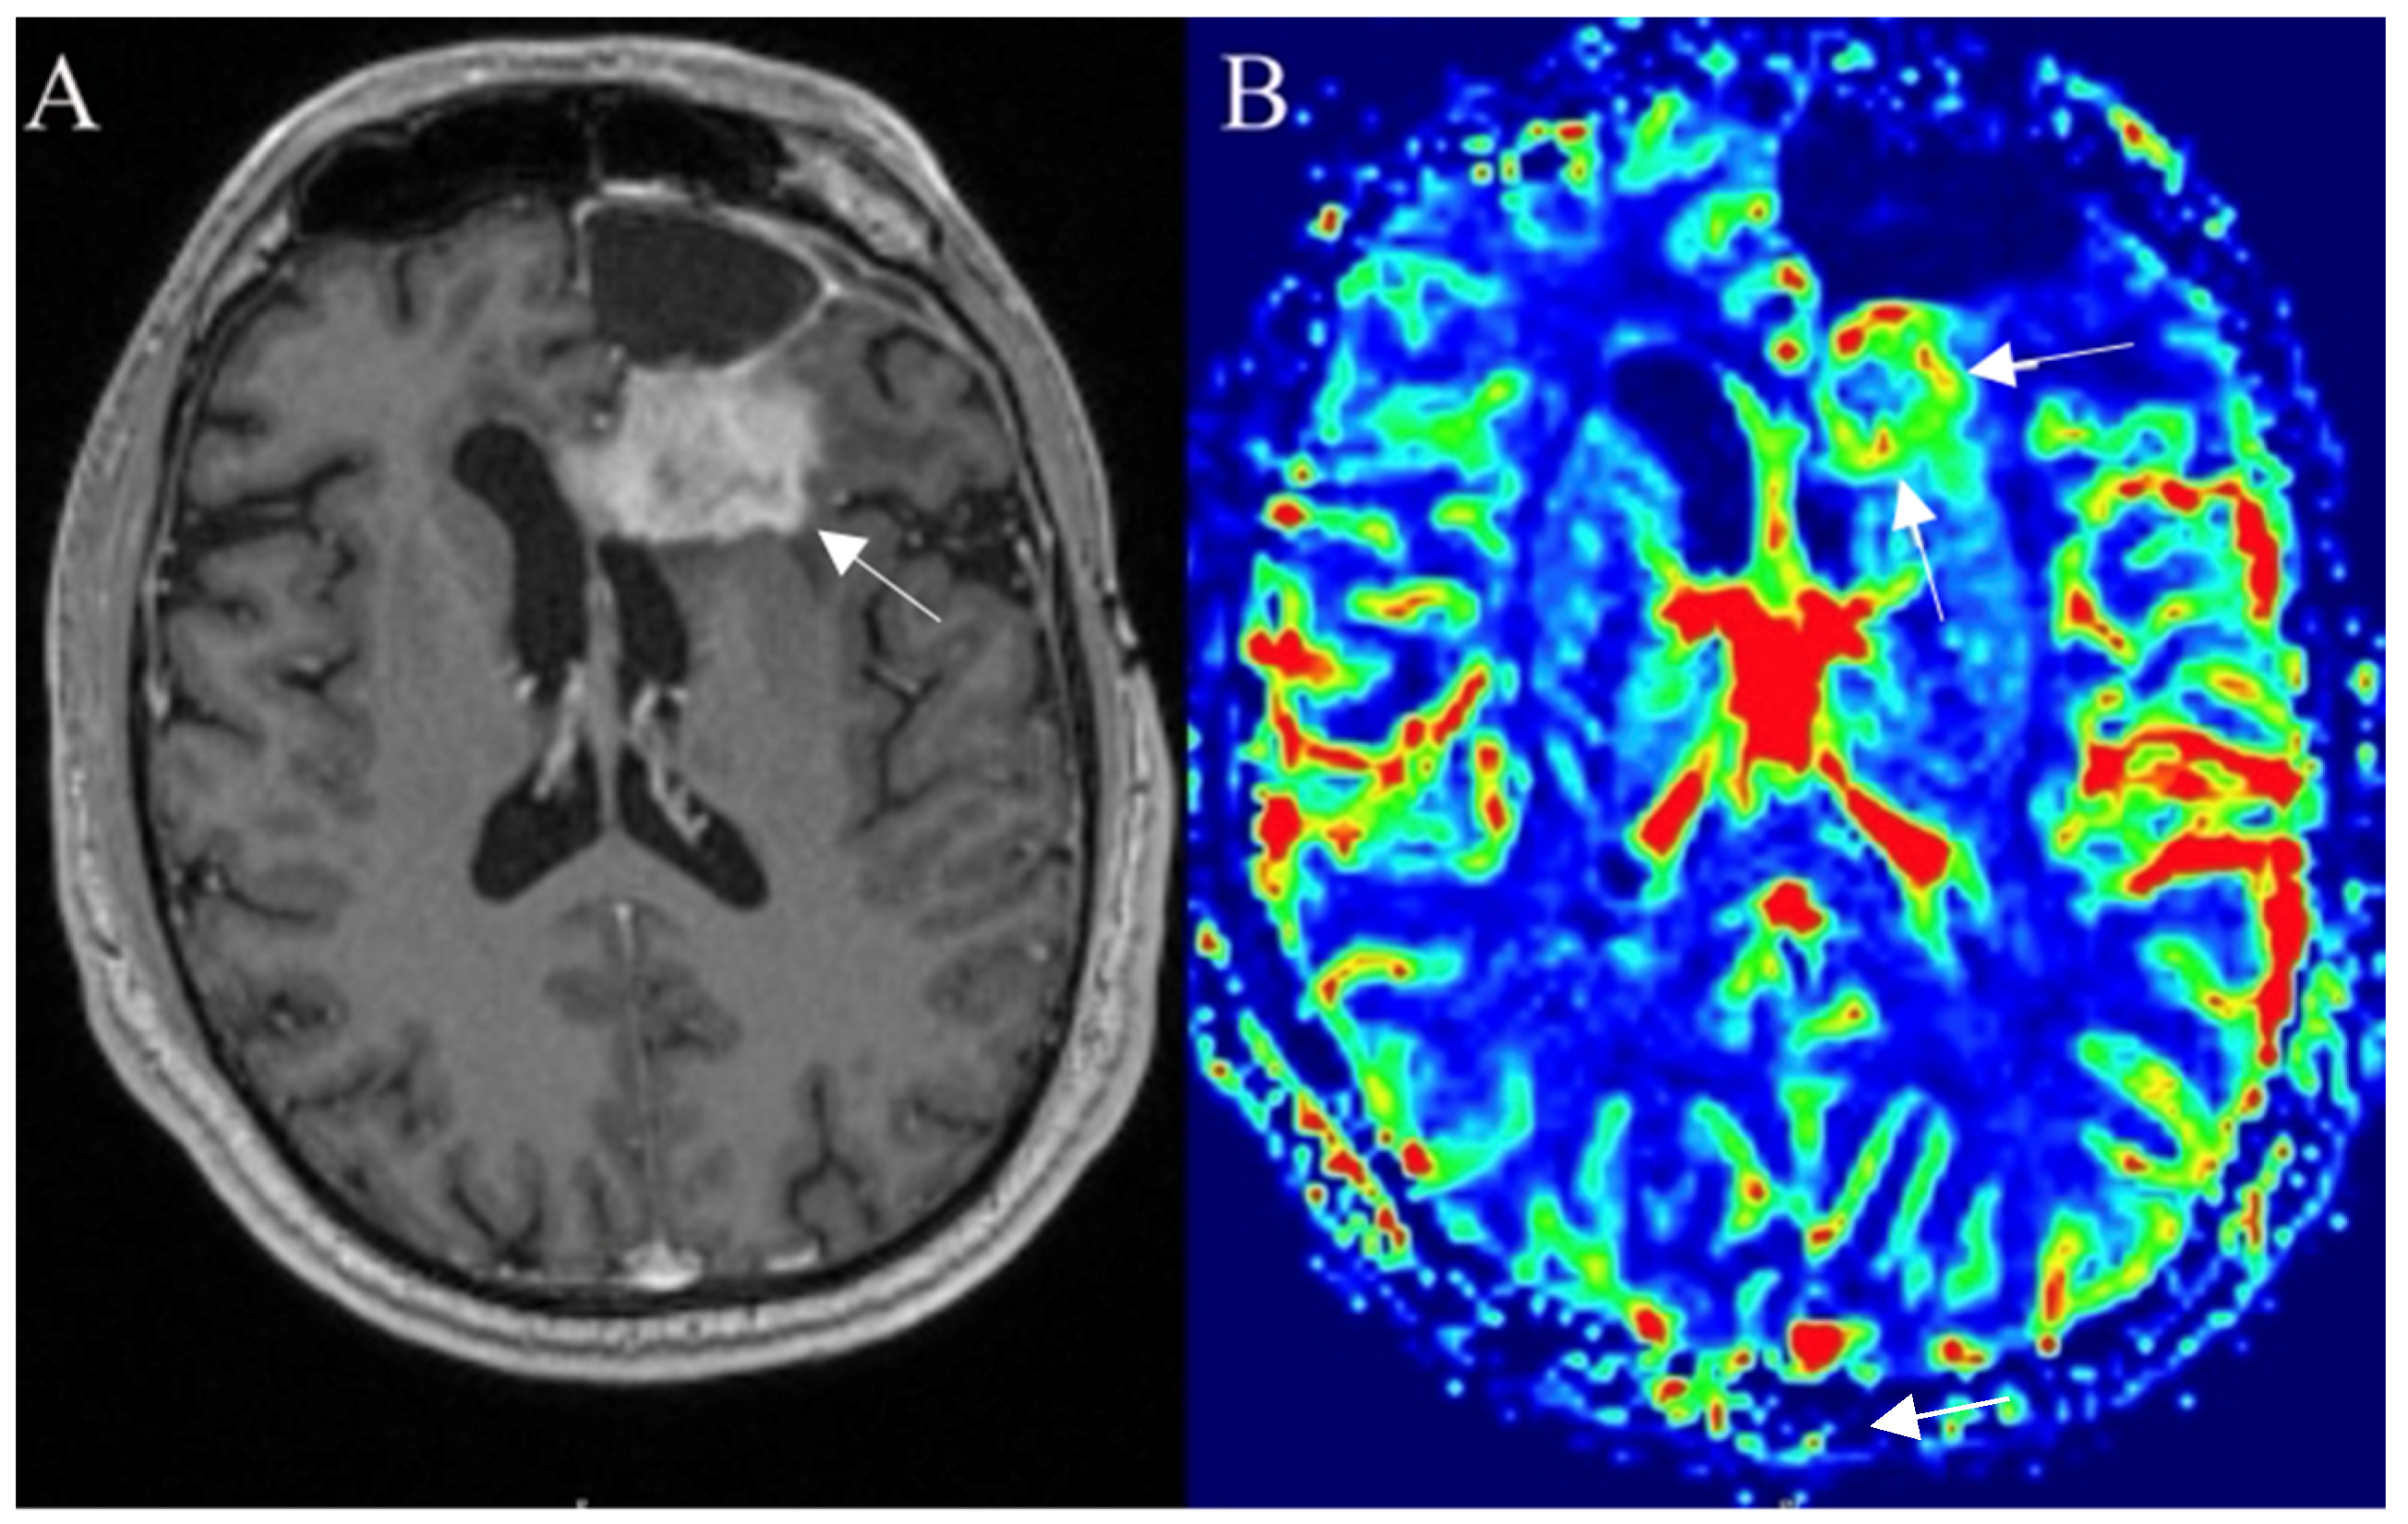

3.3. Perfusion-Based Imaging

3.3.1. Dynamic Susceptibility Contrast

3.3.2. Dynamic Contrast Enhancement

3.3.3. Arterial Spin Labelling